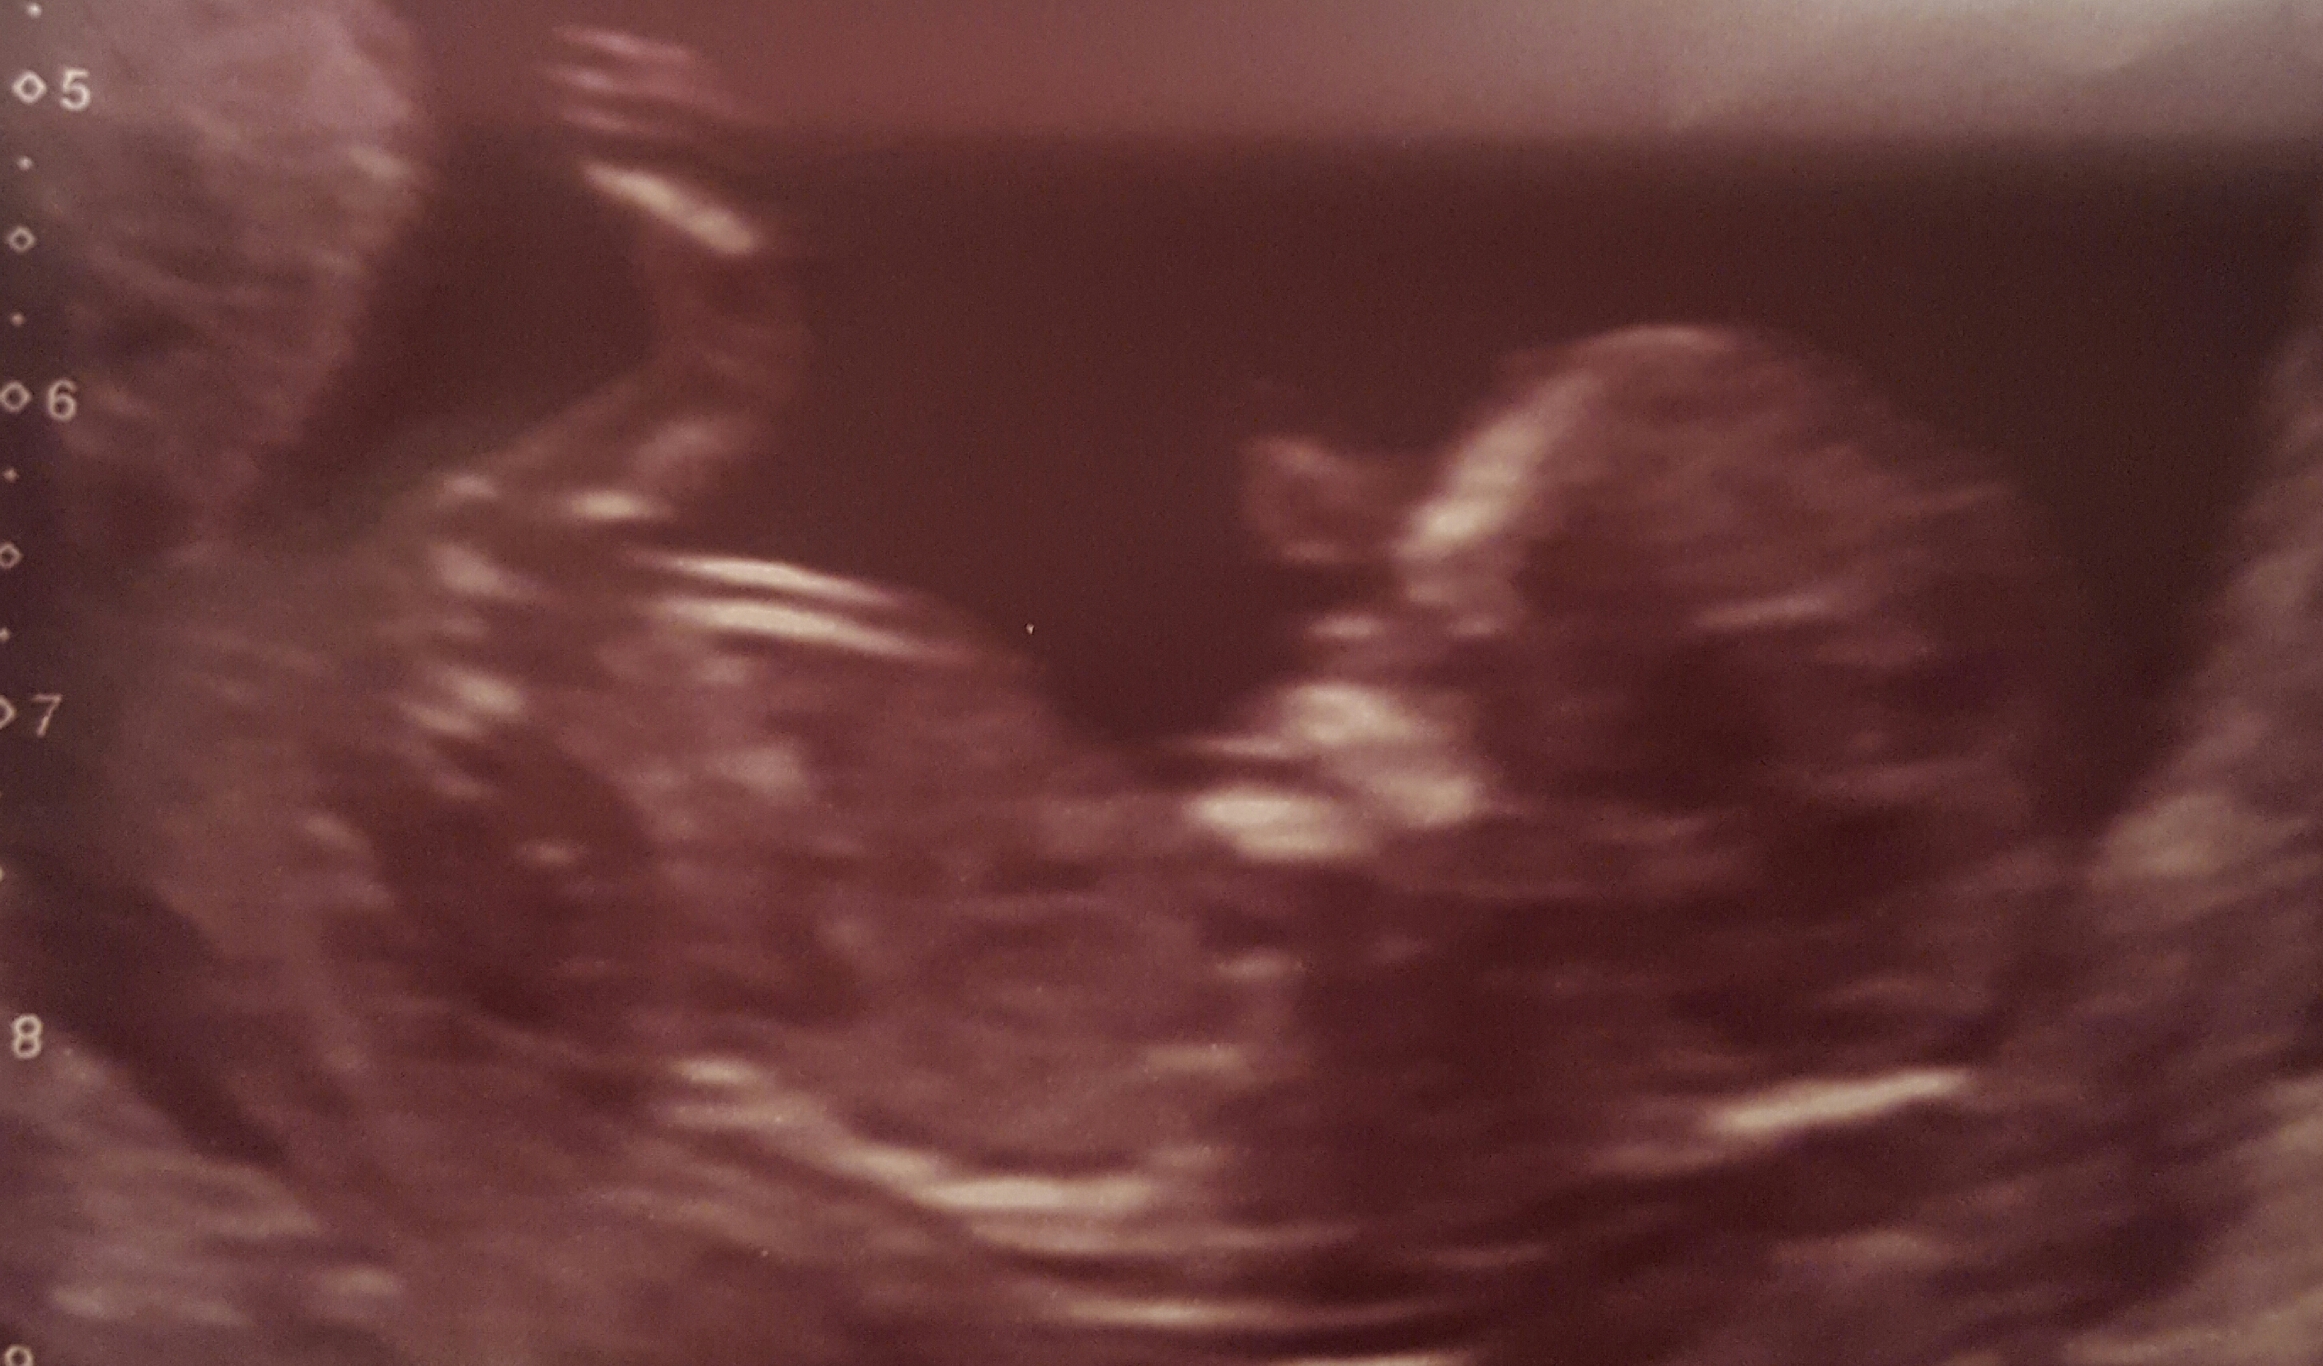

Avril, top pic of your new pics looks very boyish, the leg may have been obscuring it in your other pics, hope I'm wrong:luck: I would have guessed girl off of your original pic also.

Thanks elp. Im especially confused on that one cos i asked sonographer where the nub was and she pointed to that bit but said its not reliable as cord was there too and even showed us it pulsating. It was the bit on the very top of it that was pulsing. The rest wasnt.

Sorry, that is a very boyish nub. I would be very surprised if this was a girl. So sorry you got all those girl guesses, I don't think that the straight line in the first pic is a nub, the nub is higher and hidden by the leg. Your second pic shows a perfect boy nub. Congrats with baby! :awe:

Aaah! thats interesting Avril. With my last I had a similar scan, the cord was pulsing exactly in the nub area which on video made it look girly to me and others but in the still photos looked boy, mine turned out to be a boy but after all so the cord must have been sitting on the boyish part of the nub. Yours could well easily go either way knowing this, do you have any video?? I'll add my video if you want to see:)

The second pic really looks like a boy nub to me